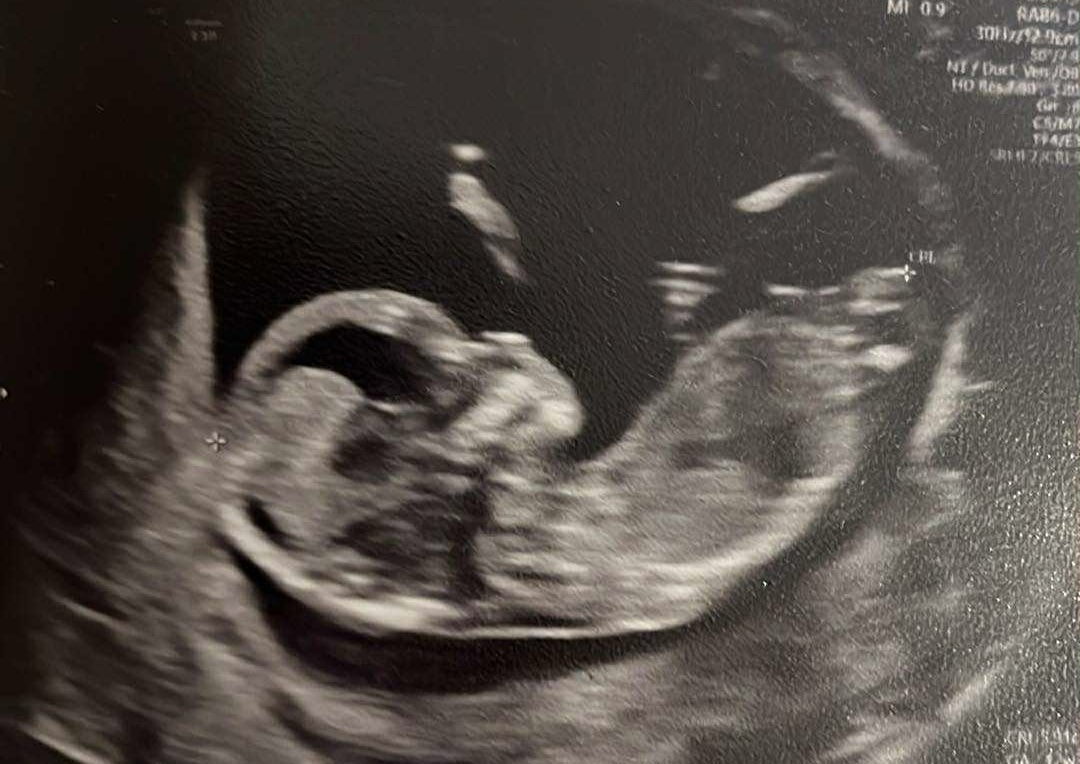

Byłam dzis na USG

dzieciaczek ma 4,46 cm i wg wielkości jest o tydzień starszy niż wg OM😮 no ale pierwszy syn też jest wysoki więc może znowu geny taty robią robotę, choc oczywiście już się pojawiają myśli czy coś jest nie tak, kobiety w ciąży chyba zawsze będą się martwić 😅 serduszko 164 uderzenia na minutę. Trochę do tej pory myślałam, że skoro mam tyle objawów, których nie było przy synu to będzie dziewuszka, ale tak wierzgał nogami, że zaczynam znowu myśleć że chłopak

Dziewczyny, mam prenatalne umówione za 2 tygodni, wg okresu to 12+2, myslicie że będzie ok nawet jesli wg USG jest dziecko o tydzień większe? Czy próbować przekładać na wcześniej?